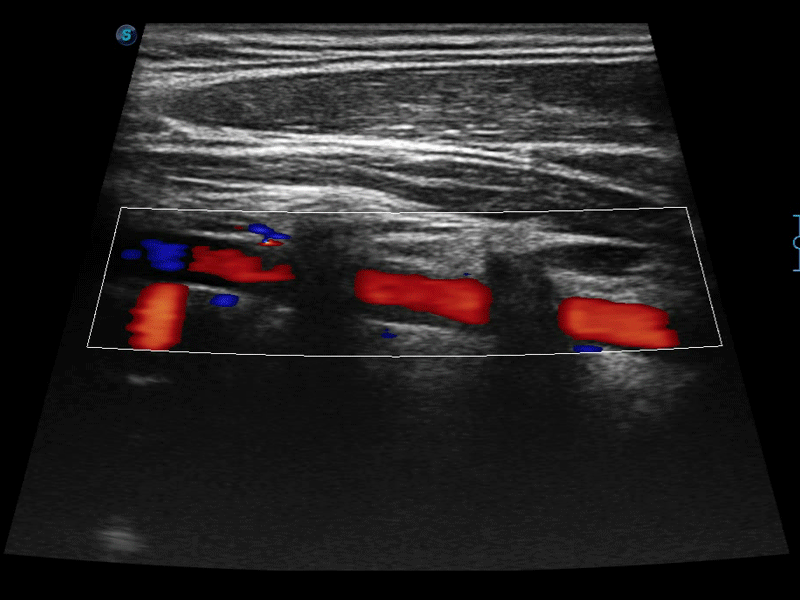

高分辨率血流成像技術(shù)提高了對(duì)低速血流信號(hào)的檢測(cè)能力。在提高空間分辨率的同時(shí),也克服了血流外溢現(xiàn)象,為用戶(hù)提供更加真實(shí)的血流動(dòng)力學(xué)信息。

通過(guò)色彩血流和實(shí)時(shí)寬景相結(jié)合,可觀察到完整的靜脈或動(dòng)脈的血流,方便醫(yī)生檢查。實(shí)時(shí)掃查過(guò)程中,如有任何操作失誤也可以很容易地進(jìn)行回掃擦除,而不會(huì)中斷掃查。